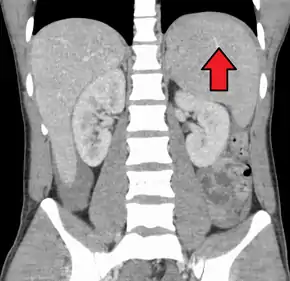

Spleen enlargement is common in the second and third weeks, although this may not be apparent on physical examination. Rarely the spleen may rupture.[24] There may also be some enlargement of the liver.[22] Jaundice occurs only occasionally.[14][25]

Splenomegaly is a common symptom of infectious mononucleosis and health care providers may consider using abdominal ultrasonography to get insight into the enlargement of a person's spleen.[58] However, because spleen size varies greatly, ultrasonography is not a valid technique for assessing spleen enlargement and should not be used in typical circumstances or to make routine decisions about fitness for playing sports.[58]